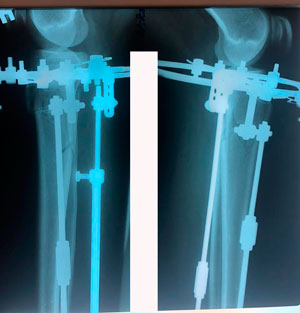

Исходник - 40 лет

Диагноз: варусная деформация голеней + Ротация с обеих сторон.

Дата операции - 09.07.2020